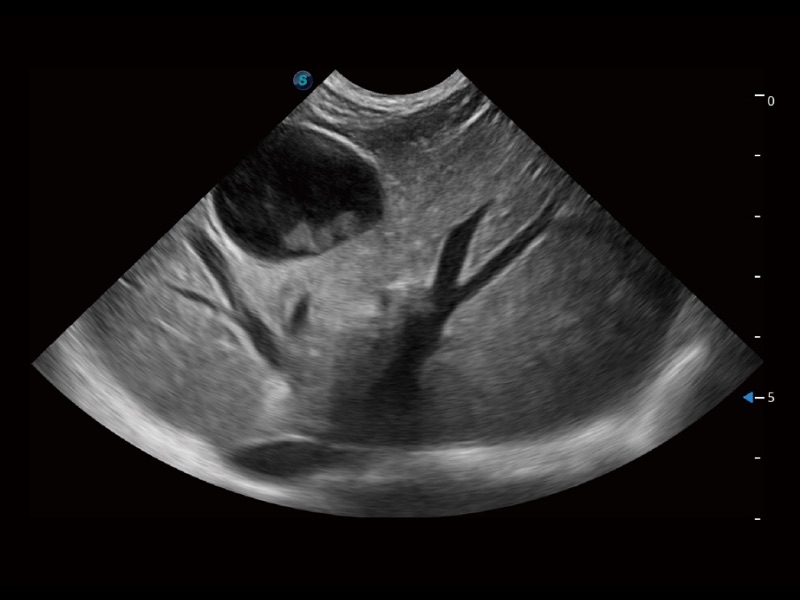

ProPet 70 进一步提升了微米成像算法,更加注重对基础原始图像的还原和保留,在有效减少斑点噪声、增强组织边界显示的同时,避免过度优化丟失真实的解剖信息。

ProPet 70专为动物医生设计,对不同的动物体型和生理结构作出了针对性的优化。通过动物影像专用软件,可满足个性化的应用需求,帮助动物医生获得更精确的诊断数据。

为精细结构及组织边缘提供高清晰度的图像和更大的成像视野。帮助减轻医生的用眼疲劳,快速精准获得测量的数据。